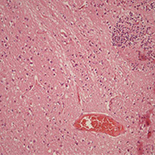

This study included 40 adult male Sprague-Dawley rats randomized into 4 groups, each of which contained equal numbers of animals. The control group had no head trauma and thus was not treated. The trauma group had head trauma but was not treated. The pregabalin group had no head trauma but was treated by pregabalin. The trauma + pregabalin group had head trauma treated with pregabalin. The biopsy samples taken from the study animals were histopathologically examined for the presence of edema, inflammation, and neuronal damage.

All animals in the trauma group had edema, inflammation, and neuronal damage. Four subjects in the control group, 6 in the pregabalin group, and 4 in the trauma + pregabalin group had edema; inflammation was present in 1 subject in the control group, 3 subjects in the pregabalin group, and 3 subjects in the trauma + pregabalin group; neuronal damage existed in 1 subject in the control group, 1 subject in the pregabalin group, and 6 subjects in the trauma+pregabalin group. The trauma group had significantly higher edema and neuronal damage scores than the other groups. Similarly, inflammation was significantly more prevalent in the trauma group than the control and trauma+pregabalin groups.